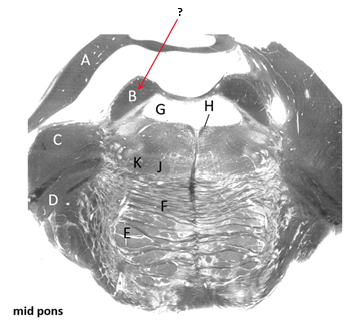

Name this and state its pathway.

Fourth ventricle.

Third ventricle–>4th ventricle–> subarachnoid space.